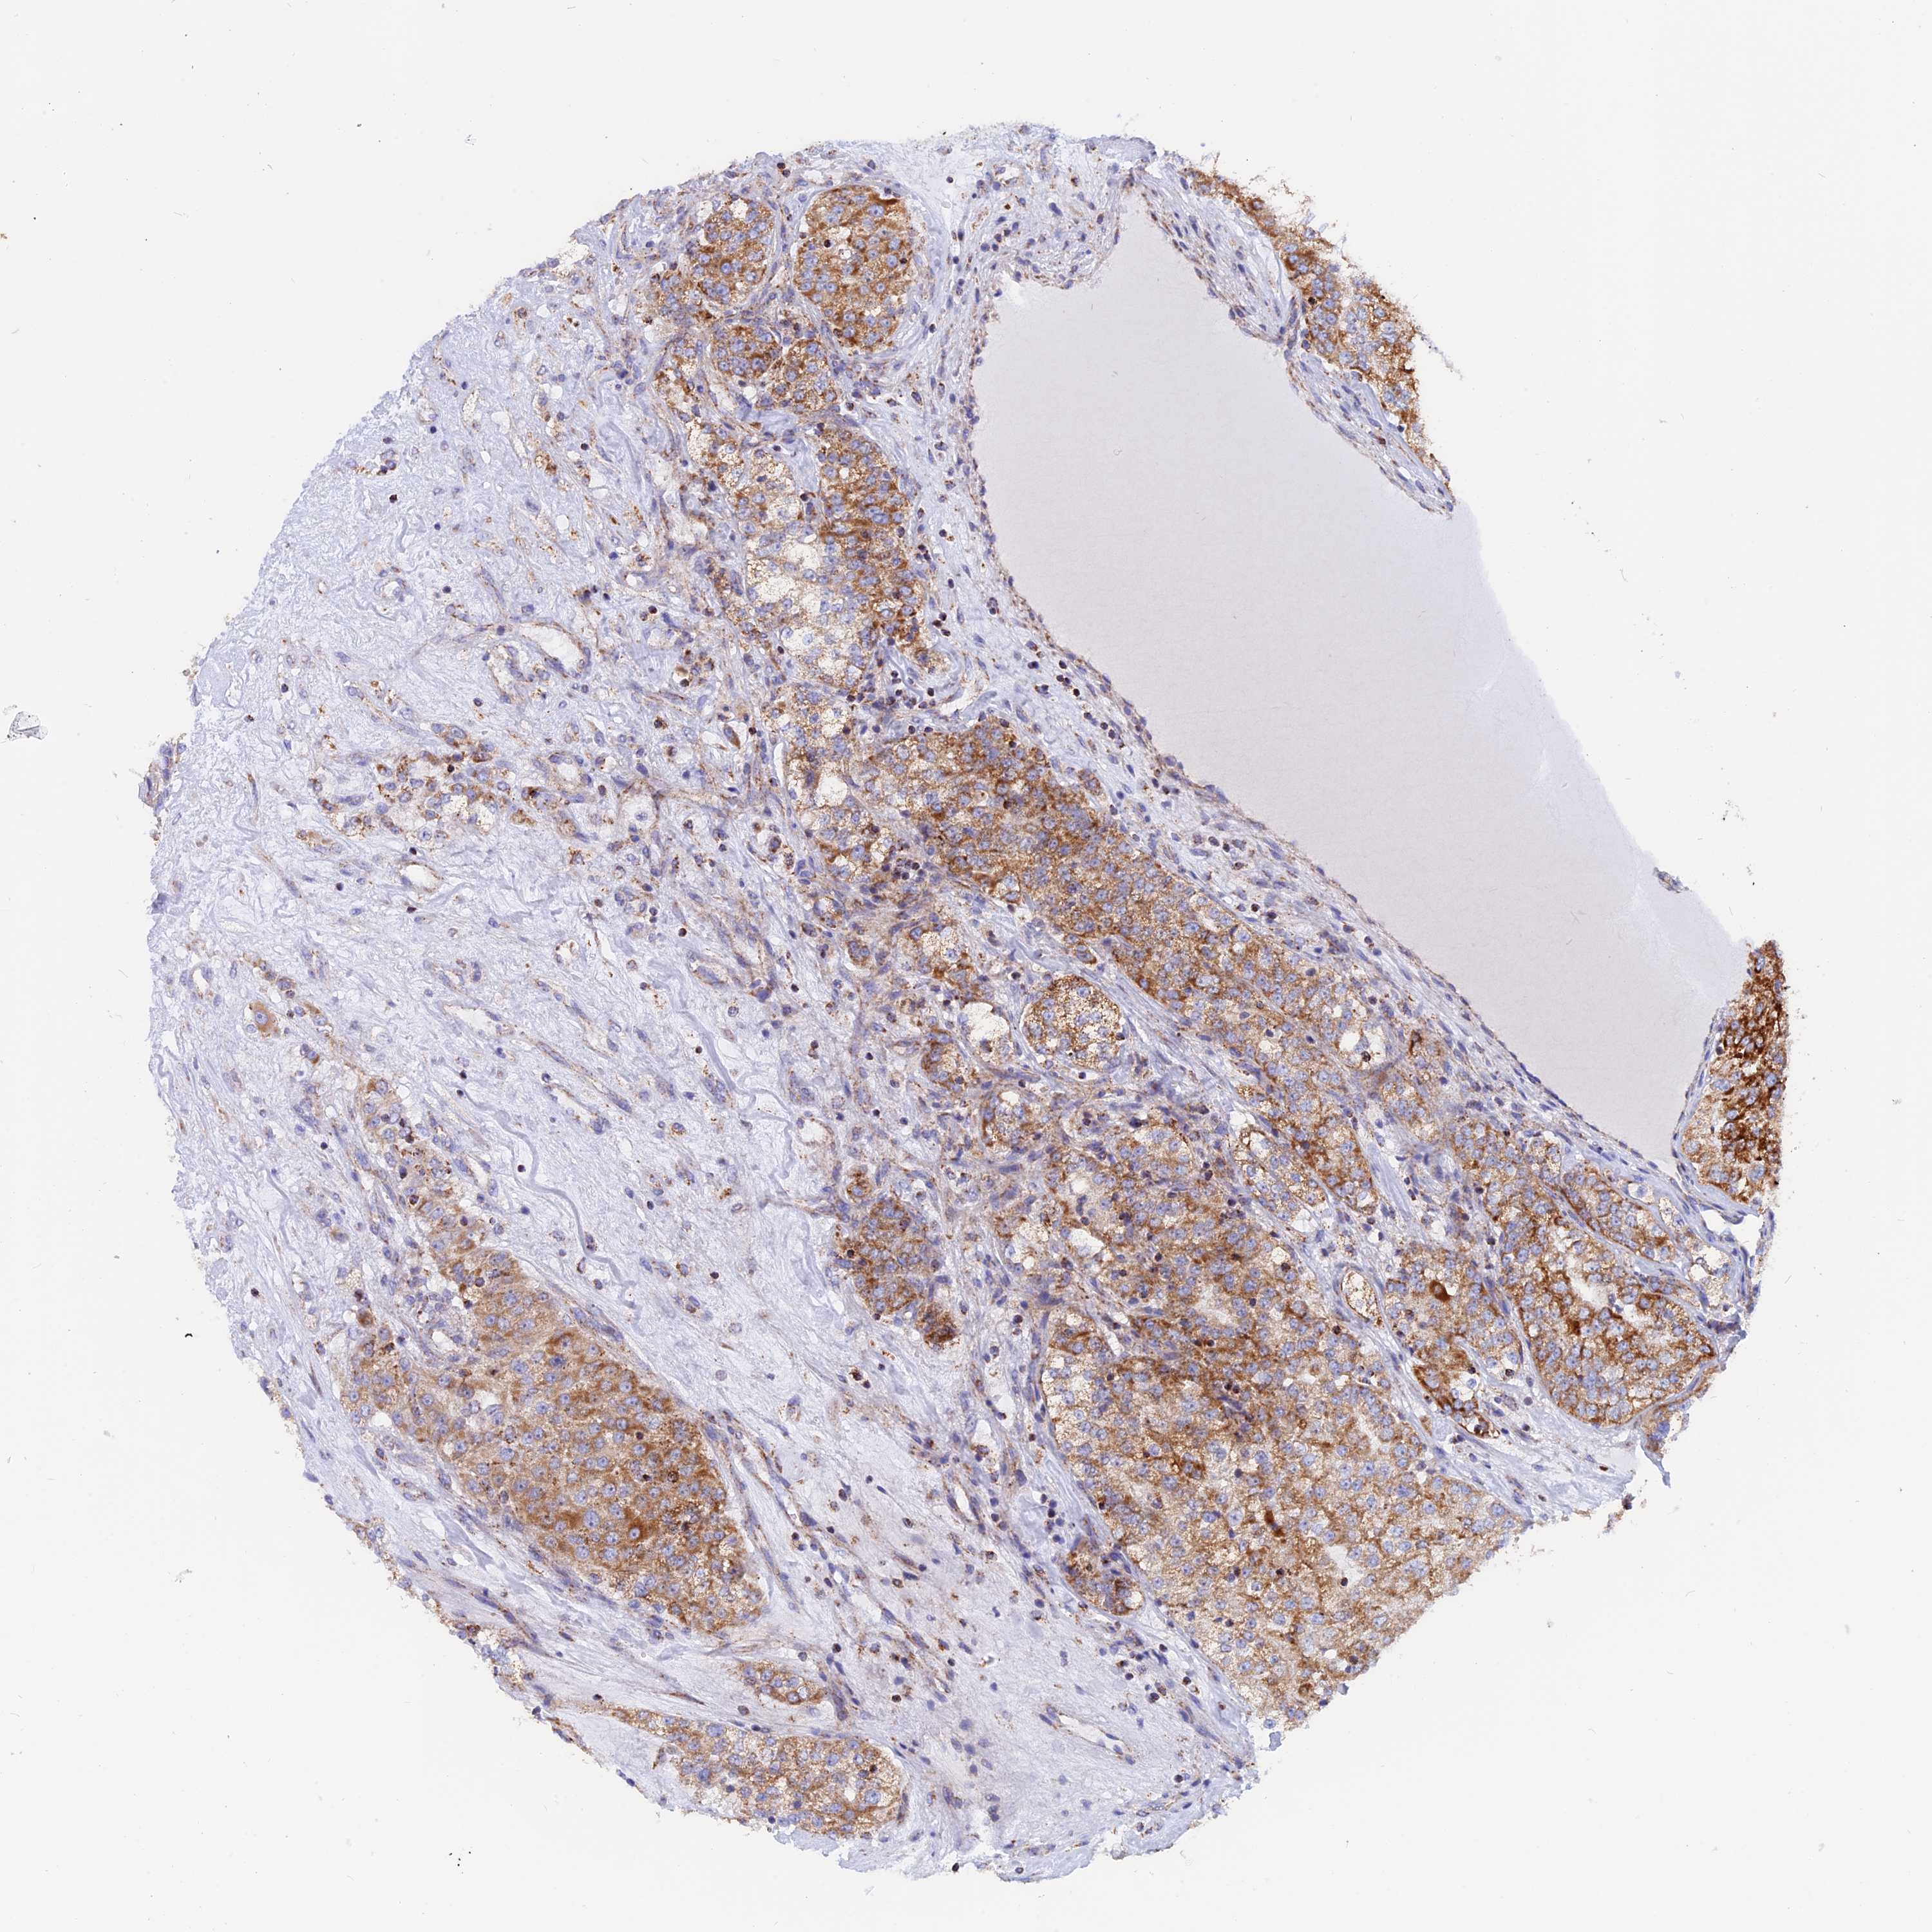

KIDNEY RENAL PAPILLARY CELL CARCINOMA (TCGA) - Interactive survival scatter ploti

The Survival Scatter plot shows the clinical status (i.e. dead or alive) for all individuals in the patient cohort, based on the same data that underlies the corresponding Kaplan-Meier plots. Patients that are alive at last time for follow-up are shown in blue and patients who have died during the study are shown in red.

The x-axis shows the expression levels (FPKM) of the investigated gene in the tumor tissue at the time of diagnosis. The y-axis shows the follow-up time after diagnosis (years). Both axes are complimented with kernel density curves demonstrating the data density over the axes. The top density plot shows the expression levels (FPKM) distribution among dead (red) and alive patients (blue). The right density plot shows the data density of the survived years of dead patients with high and low expression levels respectively, stratified using the cutoff indicated by the vertical dashed line through the Survival Scatter plot. This cutoff is automatically defined based on the FPKM cutoff that minimizes the p-score. The cutoff can be changed by dragging the vertical line or by entering a cutoff value in the square labeled "Current cut-off".

Under the Survival Scatter plot the p-score landscape (black curve; left axis) is shown together with dead median separation (red curve; right axis). Dead median separation is the difference in median mRNA expression between patients who have died with high and low expression, respectively. It is calculated as follows: median FPKM expression of dead patients with high expression - median FPKM expression of dead patients with low expression. This is intended to aid the user in visually exploring custom cutoffs and the associated p-scores and dead median separation.

Individual patient data is displayed and can be filtered by clicking on one or more of the category buttons on the top of the page. Categories describing expression level and patient information include: high, low, alive, dead, female, male and tumor stages. The scale of the x-axis can be toggled between linear and log-scale by clicking on the "x log" button. Mouse-over function shows TCGA ID, patient information and mRNA expression (FPKM) for each patient.

& Survival analysisi

Kaplan-Meier plots summarize results from analysis of correlation between mRNA expression level and patient survival. Patients were divided based on level of expression into one of the two groups "low" (under cut off) or "high" (over cut off). X-axis shows time for survival (years) and y-axis shows the probability of survival, where 1.0 corresponds to 100 percent.

GCDH is potential prognostic, high expression is favorable in Kidney Renal Papillary Cell Carcinoma (TCGA)

Best expression cut offi